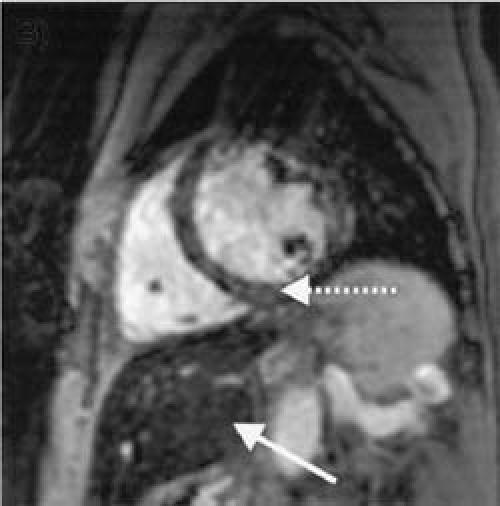

Fig. 1 Patient 1: Hemochromatosis with cardiomyopathy, but without myocardial iron deposition. A short-axis view of the heart reveals moderate hepatic iron deposition (solid arrow; hepatic T2*, 11 msec [normal, >19 msec]) manifested by a relatively dark liver parenchyma. Conversely, the cardiac muscle remains relatively bright, indicating that there is no iron deposition in the myocardium (dotted arrow; cardiac T2*, 49 msec [normal, >20 msec]). However, the left ventricle is enlarged, and there is severe global left ventricular systolic dysfunction (ejection fraction, 0.17; end-diastolic volume, 441 cc).

In Patient 1, there was severe global dysfunction, but no significant myocardial iron deposition despite moderate hepatic deposition. Coronary angiography revealed nonobstructive disease, suggesting a diagnosis of idiopathic dilated cardiomyopathy. Patient 2 had moderate global reduction in ejection fraction and severe myocardial and hepatic iron deposition, suggesting a cause for the LV dysfunction.